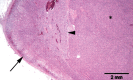

Diagnostics: In any cat presenting with hypokalaemia and/or arterial hypertension, other potential causes should be excluded. The ratio of plasma aldosterone concentration to plasma renin activity (aldosterone:renin ratio) is currently the best screening test for feline primary hyperaldosteronism. Diagnostic imaging is required to differentiate between adrenocortical neoplasia and bilateral hyperplasia, and to detect any distant metastases.

Clinical challenges: The differentiation between adrenocortical neoplasia and bilateral hyperplasia is imperative for planning optimal therapy, but the limited sensitivity of diagnostic imaging may occasionally pose a problem. For confirmed unilateral primary hyperaldosteronism, unilateral adrenalectomy is the treatment of choice, and offers an excellent prognosis, but potentially fatal intra- and postoperative haemorrhage is a reported complication and risk factors have yet to be identified.